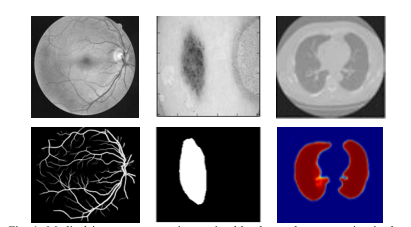

本研究展示了两种改进的分割模型,一种使用递归卷积网络,另一种使用递归残差卷积网络。为了实现我们的目标,我们对所提出的模型在不同的医学想象模式上进行了评估,如图1所示。这项工作的贡献可概括如下:

1) 介绍了两种新的医学图像分割模型RU-Net和R2U-Net。

2) 实验在视网膜血管分割、皮肤癌分割和肺部分割三种不同的医学影像模式上进行。

3) 对提出的模型进行了性能评价,分别对基于斑片的视网膜血管分割任务和端到端图像分割方法进行了皮肤病变和肺部的分割任务。

为了证明RU-Net和R2U-Net模型的性能,我们在三个不同的医学影像数据集上对它们进行了测试。这些包括从视网膜图像中分割血管(如图6所示的DRIVE、STARE和CHASE_DB1)、皮肤癌病灶分割和2D图像中的肺分割。对于这个实现,Keras和TensorFlow框架在一台拥有56G RAM和NIVIDIA GEFORCE GTX-980 Ti的GPU机器上进行实验。